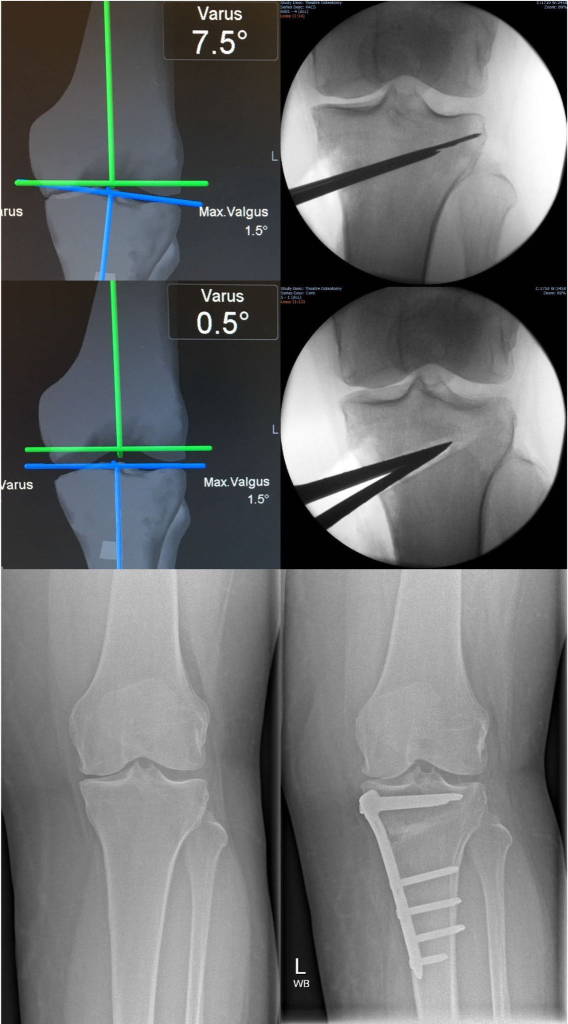

Osteotomies and joint preservation

Partial and total knee replacement

Robotic joint replacement